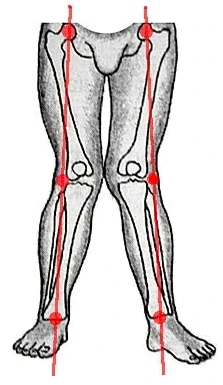

What Are Knock Knees? Causes & Treatment Options

“Knock knees” is a term used to describe the medical term genu valgum, which means the knees fall inside the midline of the legs.

What are bowed-legs?

“Bowed legs” is a term used to describe the medical term genu varum, which means the knees fall outside the midline of the legs.